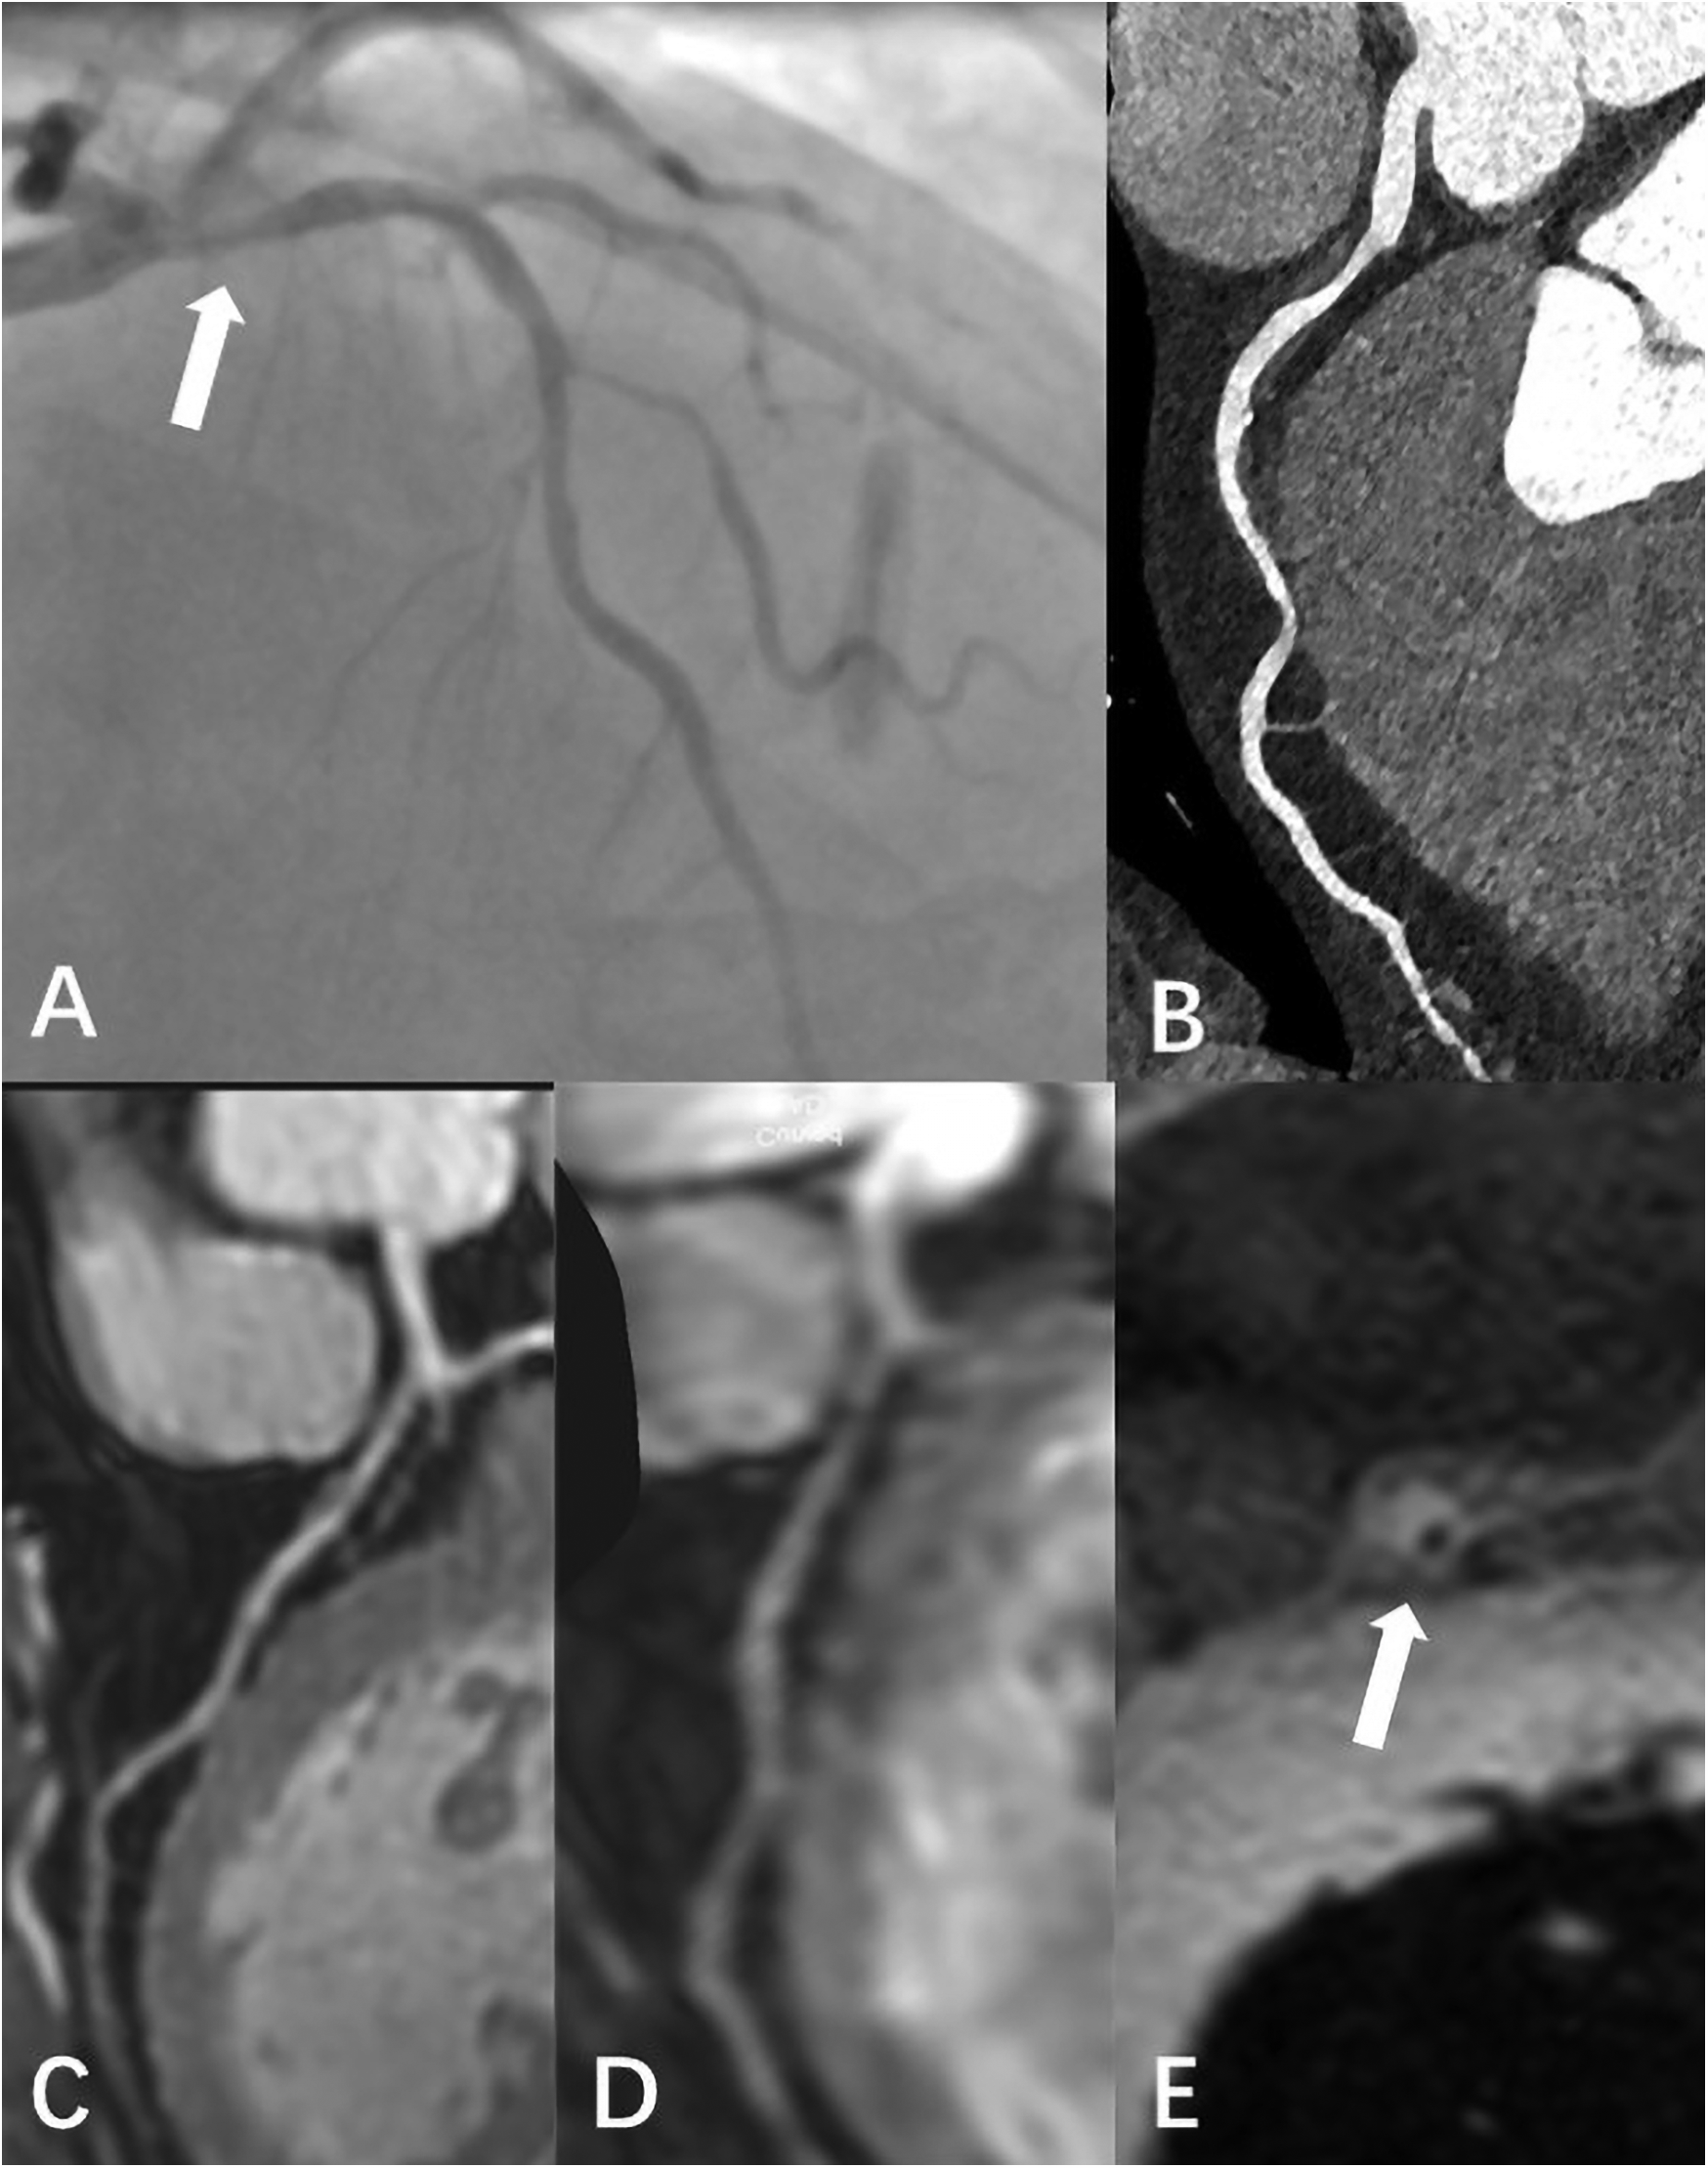

Figure 6

Male, 59 Y, with chest pain. (A) Catheter-based x-ray coronary angiography indicated a 70% stenosis at the origin of the LAD. (B) CTA revealed non-calcified plaque surrounding the lumen at the proximal LAD, with moderate stenosis. (C) 3D BTFE showed a localized signal reduction in the proximal vessel wall. (D) MSG-EPI indicated moderate stenosis in the proximal lumen. (E) Axial T1-weighted fat-suppressed black-blood sequence suggested the presence of a high-signal plaque surrounding the vessel wall.